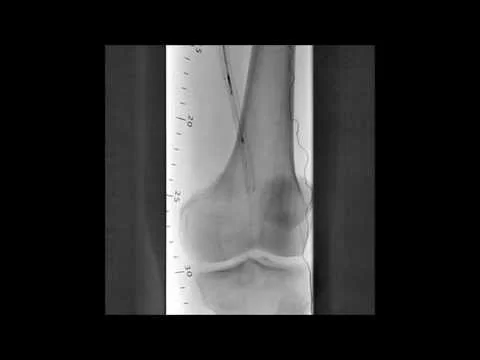

BTK CTO Viance & Enteer